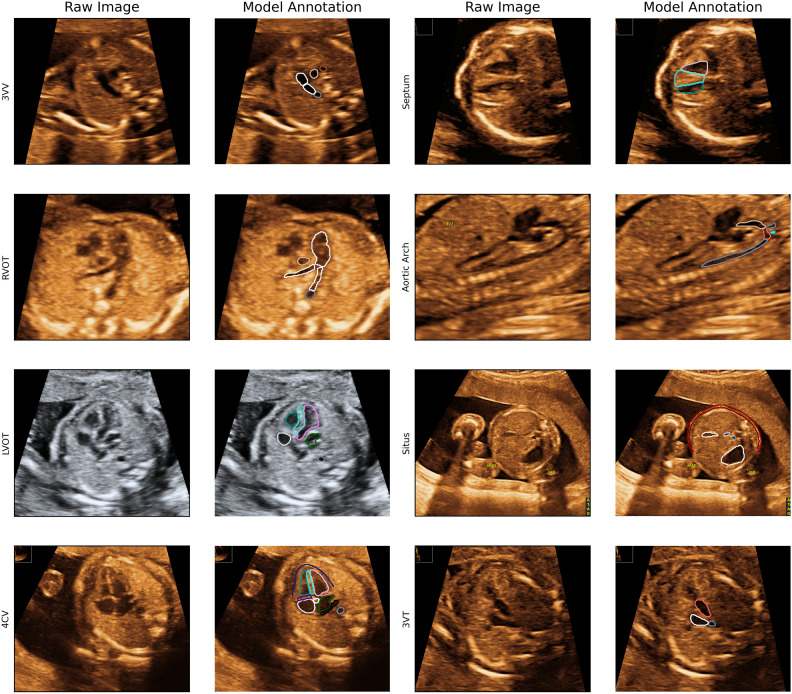

Two-dimensional ultrasound images from the retrospective dataset of the 18–22-week pregnancy scan were used to train and validate the model. The annotation included 28 different key anatomical features within eight standard planes of the fetal echocardiography scans, defined by existing international practice guidelines38. The standard planes in our model were: the four chamber view (4CV), the ventricular septum view (VSV), the right ventricular outflow tract (RVOT), the left ventricular outflow tract (LVOT), the three-vessel view (3VV), the three-vessel trachea view (3VT), the aortic arch in sagittal plane (AA) and the abdominal situs (Situs). See Fig. 2 for AI annotation and segmentation examples for all planes. The segmentation of relevant anatomical structures serves as a foundation for conducting cardiac biometric measurements and offers transparent explanations to inexperienced clinicians when they have achieved a standard plane or must identify the absent structures required for attainment. Furthermore, an image quality score (QS) was integrated in the model. The QS is a numeric value ranging from 1 to 10 based on the visualization of the structure—10 for perfectly outlined structure and 1 if the outline of the structure was not seen, 5 if the structure was visualized with a degree of shadow or blurriness. Please see Appendix 1 for a thorough description of the QS. The manual annotation was performed in LabelMe©39 (version 5.01) by a trainee in obstetrics and Ph.D. fellow in fetal medicine (CAT), in close collaboration with a fetal medicine expert (MGT) at routine quality meetings evaluating any uncertainties.

Figure 2.

Examples of model annotation per plane. 4CV 4 chamber view, 3VT 3 vessel trachea view, 3VV 3 vessel view, LVOT left ventricular outflow tract, RVOT ventricular outflow tract, VSV ventricular septum view.